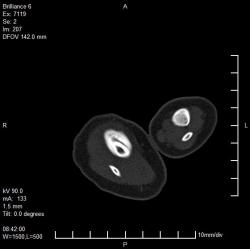

Ребенок 4 месяца. Отмечается увеличение размеров голени в течение нескольких месяцев после рождения. Травму, как бытовую, так и родовую мать отрицает. Мать обследована на ЗППП, в том числе сифилис. Выполнили рентгенографию, затем - КТ. Сначала думали о переломе и гипертрофической костной мозоли вследствие отсутствия иммобилизации, на реконструкции КТ видна как будто бы линия перелома (канал кровеносного сосуда?). Однако отсутствие положительной динамики со временем ("мозоль" не уменьшается) настораживает в плане возможной опухоли. Взяли открытую биопсию, материал пока еще в работе.

Опубликовано Валентин Катенёв в Сб, 01/24/2009 - 22:05. # Уважаемый коллега! Я совершенно не разбираюсь ни в КТ, ни в МРТ, ни в СКТ, ни в УЗИ. Но мне кажется, что в данном случае - см. вложение 11 четко дифференцируется косонаправленная прерывистость кортикального слоя б/берцовой кости - перелом? По всей видимости и гиперостоз и прочие изменения вызваны не диагностированным переломом.

Опубликовано Валентин Катенёв в Вс, 01/25/2009 - 14:28. # Уважаемая коллега! Полностью согласен с Вами по поводу "отслойки периостальных наслоений", возможно даже за счет излившейся крови (гематома). Такая махровость "периостальных наслоений" вполне может быть объяснена отсутствием иммобилизации, ибо ребенок постоянно двигает ножкой.